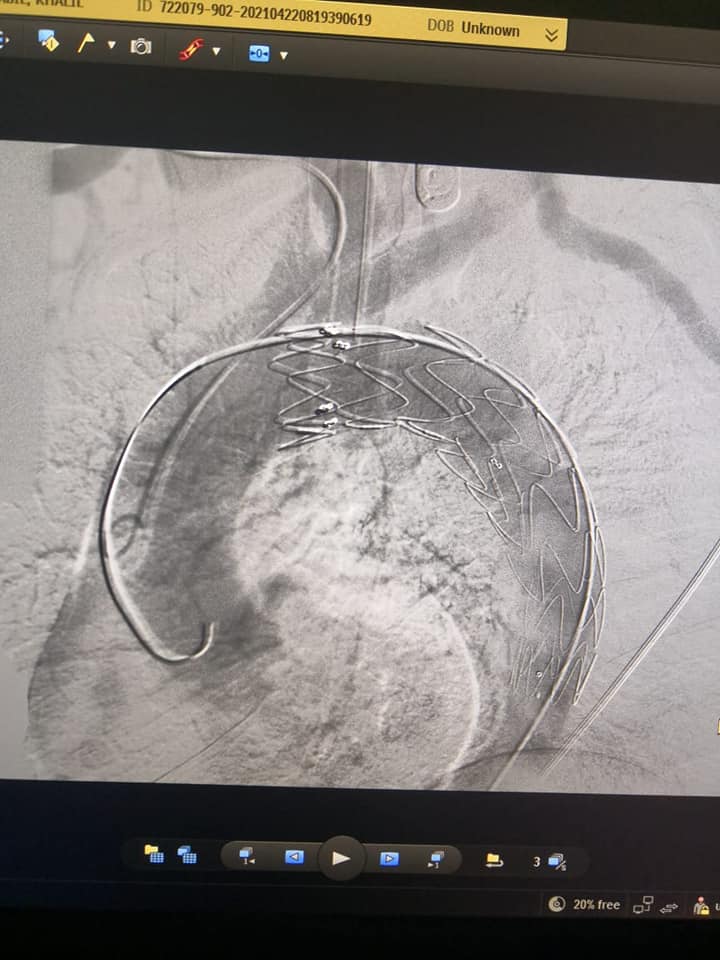

إجراء أول حالة «تيفار» بمركز جراحة الأوعية الدموية بجامعة المنصورة

قام فريق من جراحي الأوعية الدموية برئاسة الدكتور مسعد سليمان مدير مركز جراحة الأوعية الدموية، وبحضور ممثلين لجراحي القلب وفريق العناية، بإجراء قسطرة تداخلية لتصحيح انشطار بشريان الأورطي الصدري نتيجة الارتفاع المزمن بضغط المريض، وأدى الانشطار إلى تمدد بشريان الأورطي منذرا بحدوث انفجار علاوة على توقف الدورة الدموية عن بعض الأعضاء الحيوية.

و تم توفير كافة مستلزمات الجراحة بواسطة إدراة العلاج ضمن قوائم الانتظار وتم إجراء التدخل بواسطة تقنية الدعامات المغطاة والتي تضمن إعادة سريان الدم في الشريان الأورطي الرئيسي واستغرقت ٤٥ دقيقة مع توفير كافة الاستعدادات من فريق جراحة القلب وكذلك من فريق التخدير برئاسة الدكتورة دعاء جلال وفريق العناية المركزة برئاسة الدكتورة محمد عادل وأظهرت فحوصات المريض فور انتهاء الايفار بنجاح التدخل بنسبة ١٠٠٪.